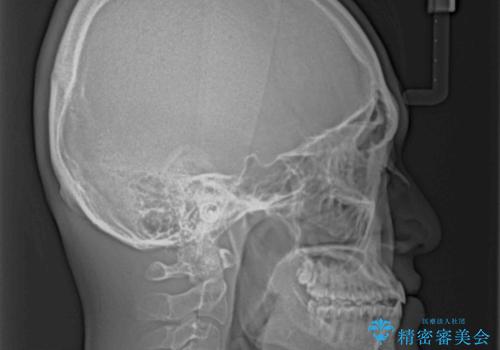

受け口傾向の骨格であり、前歯はクロスバイトまたは切端咬合となっており、叢生は警備であったため、下顎を中心に歯列全体の後方移動を行い、IPR(歯と歯の間を削る)によってデコボコが解消するように設計し、インビザラインにより治療を行うこととしました。

受け口傾向のインビザライン矯正は比較的治療を行いやすいため、きれいに仕上げることができました。舌の突出癖が顕著であったため、改善のためのトレーニングをしっかりと行っていただきました。